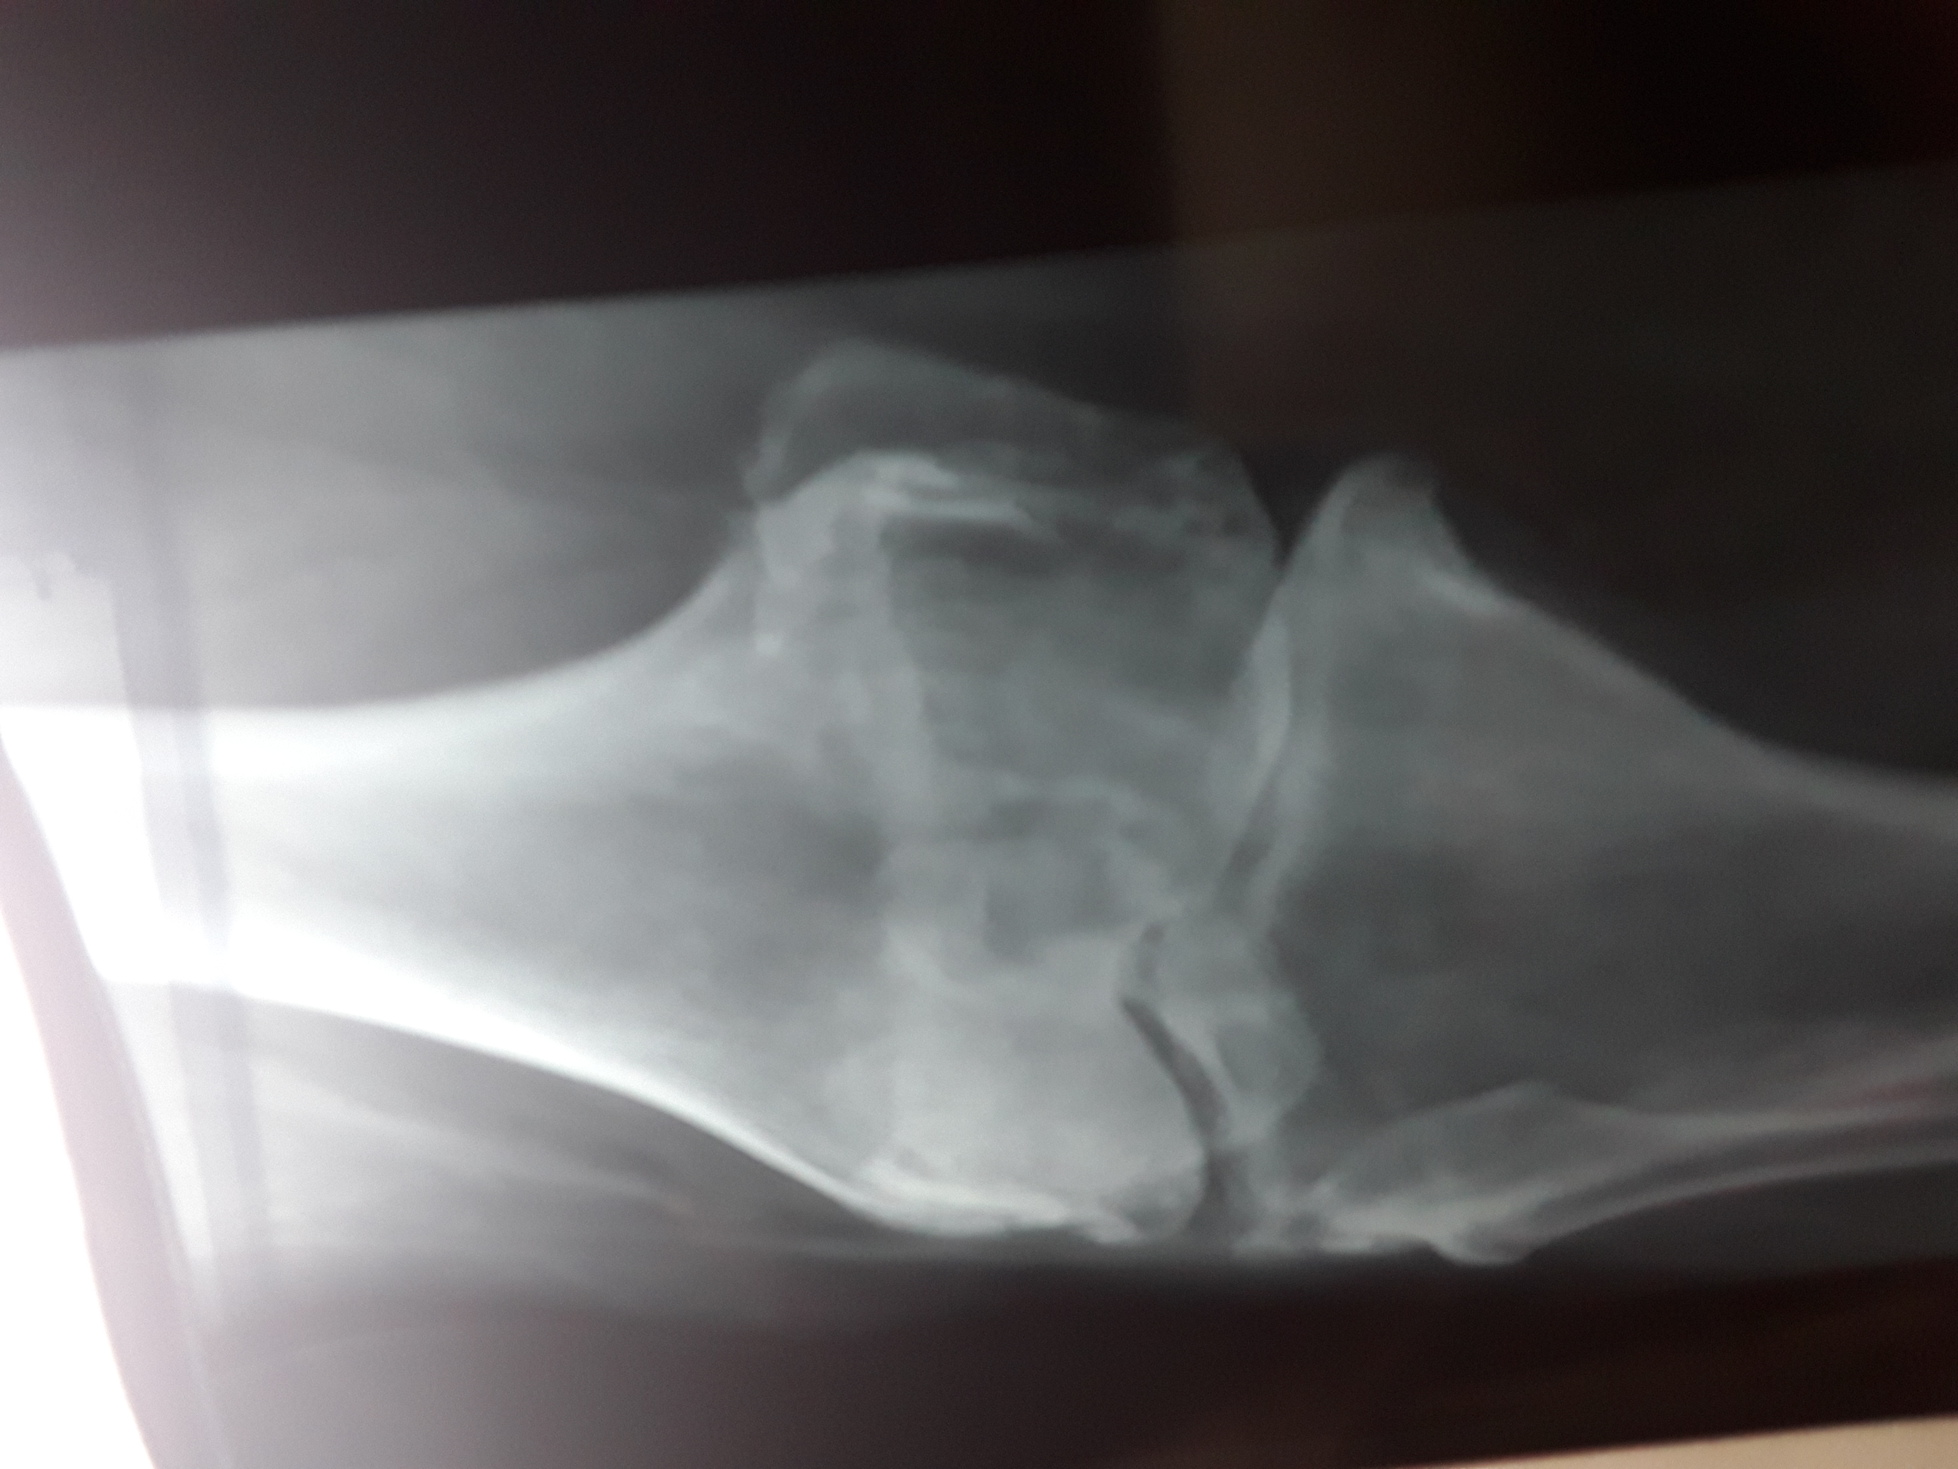

My mother has a histroy of ghout and osteoarthritis. But she is doing all chores without any support . Yetserday, she fell and her knee probably twisted . We take her to emergency ,got the x ray are given but still her knee and leg is not bearing weight. X ray are attached for opinion , is there is something to worry.

Your mom has suffering from advanced OA KNEE. IT require knee replacement surgery. During fall she probably had damaged soft tissue of the knee joint leading to swelling. At this stage please consult a nearest Rheumatologist or orthopedist for intra articular injection.